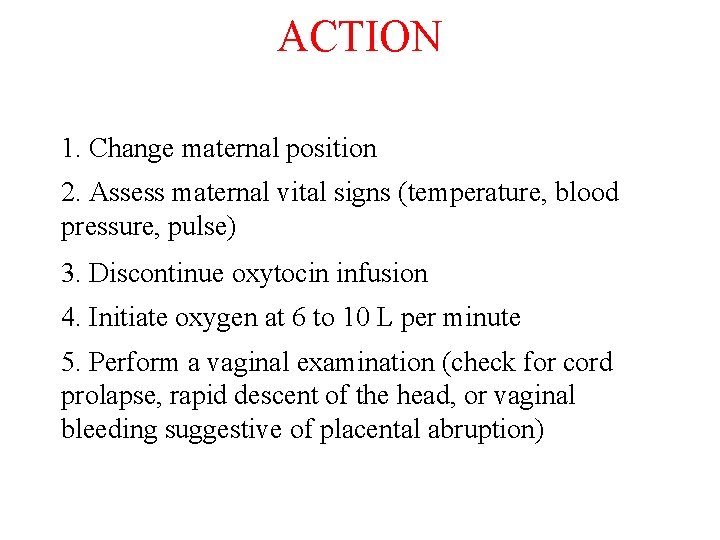

ACTION 1. Change maternal position 2. Assess maternal vital signs (temperature, blood pressure, pulse) 3. Discontinue oxytocin infusion 4. Initiate oxygen at 6 to 10 L per minute 5. Perform a vaginal examination (check for cord prolapse, rapid descent of the head, or vaginal bleeding suggestive of placental abruption)